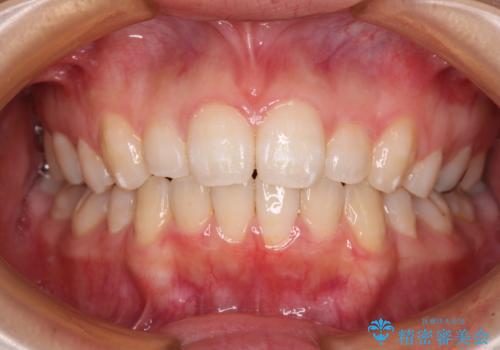

前歯をさげたい 歯を抜かずに マウスピース矯正で治したい

[ インビザライン矯正 ]マイクロインプラント用いた大きな遠心移動

担当医 大元洋佑